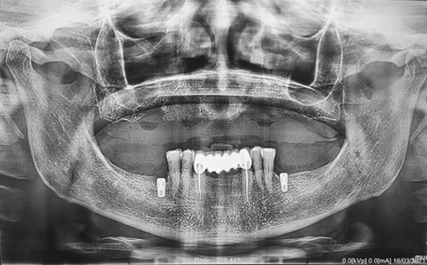

A panoramic radiograph showed a tilted implant in region of 16 with radiolucency surrounding the implant, a fractured implant in region 14, a root tip of 13 endodontic treated without apical response and implant on 23 with considerable radiolucency around it.

On the lower jaw, her right and left molars were absent, as well as anterior lower teeth, and she had 33 and 43 prepared without provisional. Two implants were placed in regions 36 and 46 (Figure 2).

Figure 2: Preoperative panoramic radiograph.

- Study of the CBCT: Implant on 16 with radiolucency (huge defect) surrounding the implant.

- Fractured implant at the region of 14.

- A root tip of 13 endodontic treated without apical response and implant 23 with considerable radiolucency around it.

- Lack of height and width of bone on the left side.

Figure 8: Panorex of the patient wearing the appliance.

Insufficient bone height on 16 and 28, Insufficient bone width on 14 and 24.

Figure 12: Panorex showing placement of 7 implants.

We chose the placement of 7 implants type Straumann without immediate loading (Figure 12). The type of the surgical guide is mucosa soft tissue supported with fixation by pins. A Flapless surgery without Bone regeneration, and a sinus Graft on 28.

We prescribe to the patient antibiotics, painkillers and rinsing the oral cavity twice a day for a week with a 0.2% chlorhexidine mouthwash. We request a panoramic radiograph after the surgery (Figure 24). We have early loss of implant 21 placed in the location previous nasopalatal cyst location.

Figure 24: Panoramic radiograph after implants placement.

We notice that the guide was placed more buccally, a complete bone regeneration at the place of the 21 and a slight bone resorption around 23.

Figure 26: Panorex after 2-years.